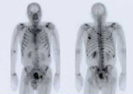

Knochenscan (Knochenszintigramm)

Knochenscan ganz

Knochenscan

Mit Knochenscans können Knochenmetastasen früher als mit Röntgenaufnahmen festgestellt werden. Sie ermöglichen dem Arzt auch, die Gesundheit aller Knochen im Körper zu überwachen, z.B. auch wie sie auf eine Behandlung ansprechen.

Zur Durchführung eines Knochenscans wird eine geringe Menge einer radioaktiven Substanz injiziert. Der markierte Stoff reichert sich für eine kurze Zeit in den Knochenarealen an, die einem erhöhtem Knochenumbau unterliegen. Da Knochenmetastasen bei Brustkrebs zu einem erhöhten Umbau des Knochens führen, können mit Hilfe der Knochenszintigraphie so die Knochenmetastasen ausfindig gemacht werden.